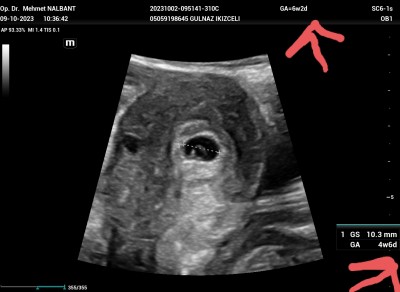

Üstteki işaretli yerdev6+2 yazıyor alttaki yerde 4 hafta 6 günlük yazıyor kafam karıştı. Böyle olan varmı geridemi anlayamadım bugün kalp atışı duyulmadi haftaya bidaha kontrol

Gebelik haftası 6+2

Senin haftan 6+2 ultrasonda 4+6 cikmis

Kese ölçümüne göre 4 hafda 6 gun gösteriyor